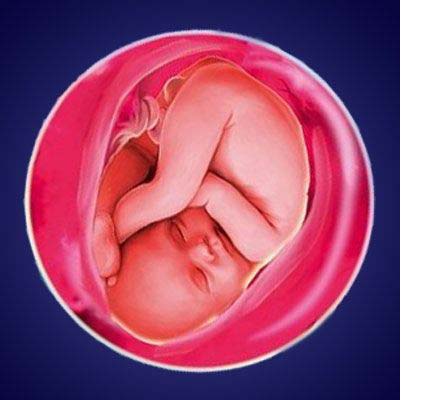

Плод 39 Недель Фото

Плод 39 Недель Фото 100 фото